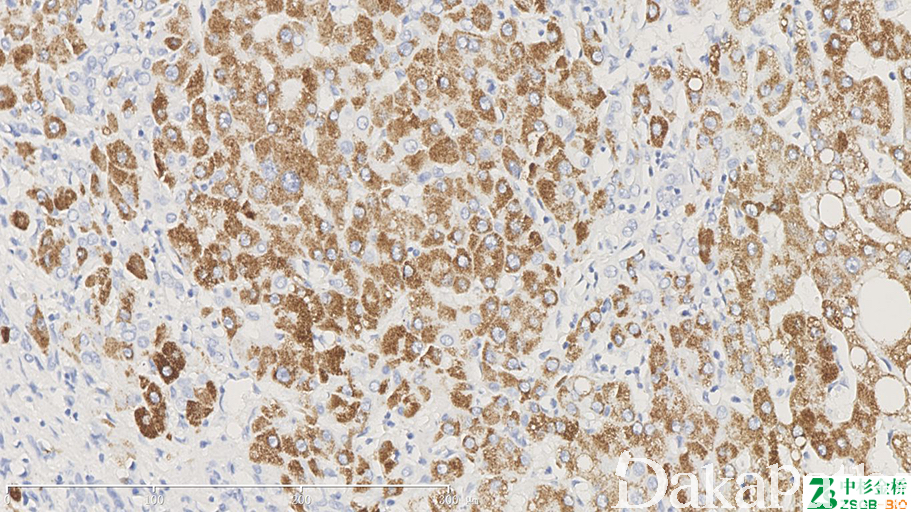

Hep-Par1

标记正常肝细胞、多数肝癌细胞。HCC 诊断中,HepPar1 是一种具有较高敏感性和特异性的标记物,它的特异性靶点在肝细胞的线粒体,可生产弥漫的颗粒状物质,胞质呈颗粒状。

信号定位: 胞质